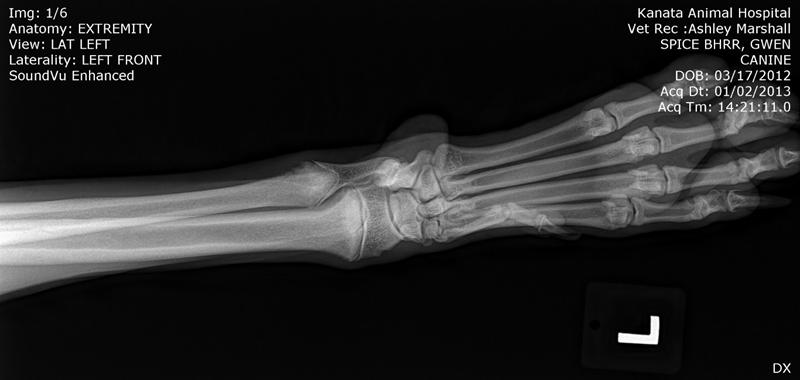

Here are BHRR's Spice's X-Rays: